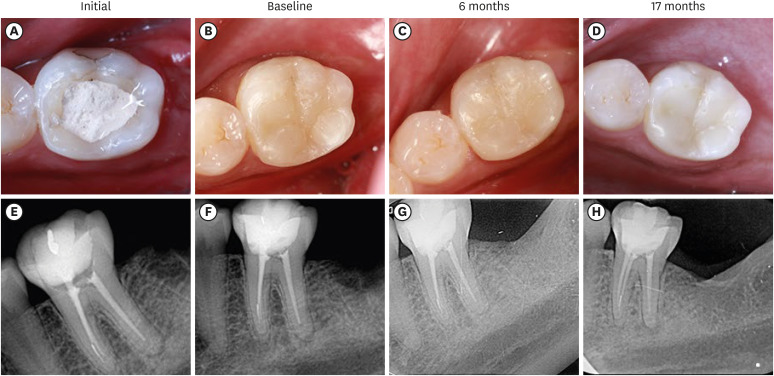

Materials and methods: The research was registered in Brazilian Registry of Clinical Trials. The randomized clinical trial involved 33 patients, each with at least 1 mandibular molar requiring restoration after receiving endodontic treatment. Patients were randomly assigned to receive either bulk-fill resin composite (Tetric N Ceram Bulk Fill, Ivoclar Vivadent) or the alkasite restorative material (Cention N, Ivoclar Vivadent). Upon completion of the restorations, 3 calibrated professionals utilized the United States Public Health Service criteria to assess various factors, including retention, secondary caries, marginal adaptation, restoration color, marginal pigmentation, and anatomical form. Evaluations were conducted at intervals of 7 days, 6 months, and 17 months. Additionally, the assessment encompassed the presence of radiolucent lines adjacent to the restoration, material deficiencies or excess, contact points, and caries recurrence. The data underwent analysis using the Friedman and Mann-Whitney tests (α = 0.05).

Results: After 17 months, the results revealed that the alkasite restorative material exhibited greater wear of anatomical shape compared to the bulk-fill resin composite (p = 0.0189). Furthermore, the alkasite restorative material significantly differed from the natural tooth color in most cases (p = 0.0000). However, no other criteria displayed significant differences between the materials or over time (p > 0.05).

Conclusions: The alkasite restorative material (Cention N) emerges as a viable option for restoring endodontically treated teeth, displaying clinically acceptable alterations after a 17-month evaluation period.